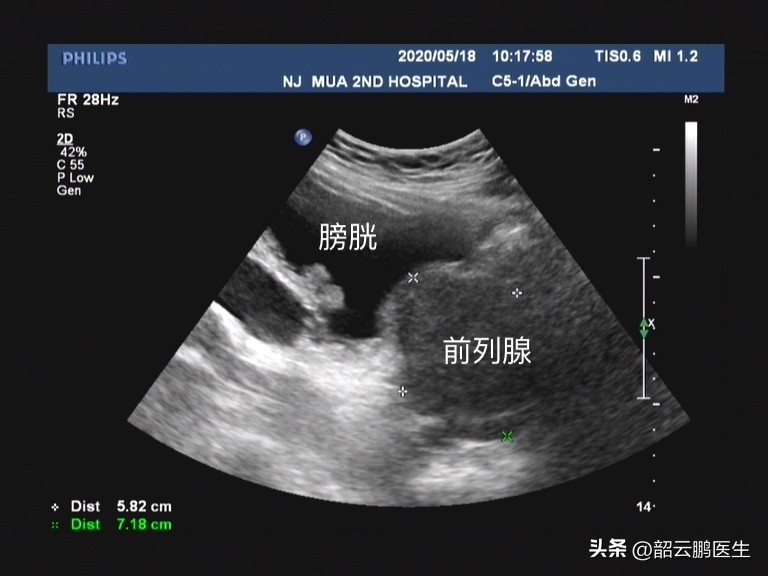

坦索罗辛是一种选择性 α1肾上腺素受体阻滞剂 ,之所以应用在前列腺增生的患者中,它的主要作用机制是 选择性阻断前列腺、尿道和膀胱颈中的α1肾上腺素受体,松弛前列腺、尿道和膀胱颈平滑肌,从而改善良性前列腺增生症所致的尿急、尿频和排尿困难等症状。

前列腺增生在老年人的发病率最高,所以 针对排尿问题应用坦索罗辛的人也以老年人为主 。虽然坦索罗辛是选择性α1肾上腺素受体阻滞剂,但是它之所以出现并发症,也是由于α1肾上腺素受体除了分布在肾脏、前列腺、膀胱括约肌外,还在 脑、心脏、血管等,其在血管平滑肌激动后的主要效应为血管收缩。